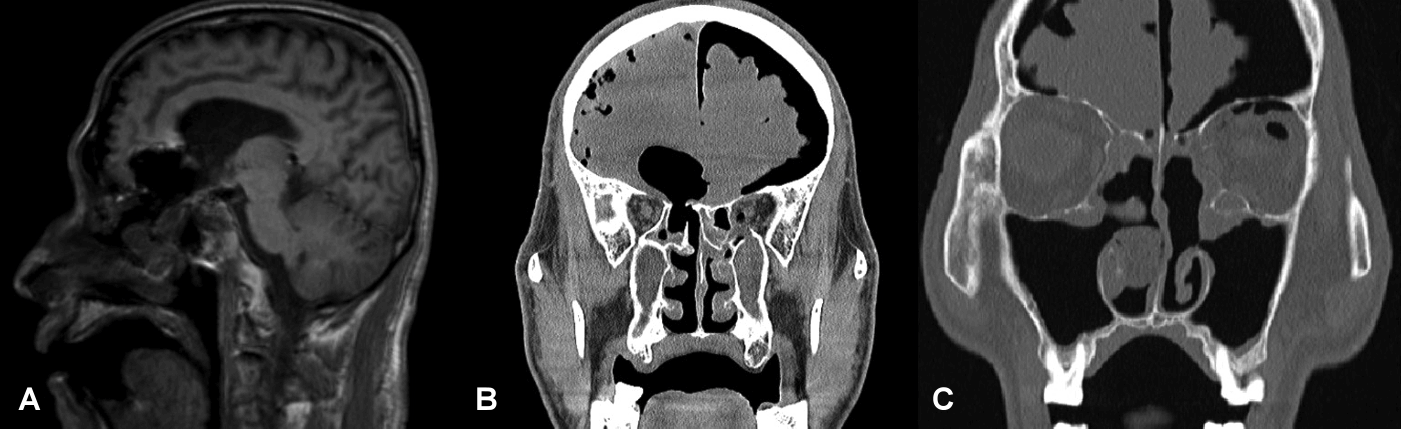

A 65-year-old male patient presented with recurring CSF leakage. Formerly in good health, aside from asthma, initial CSF leakage occurred presumably after bilateral endoscopic sinus surgery and septoturbinoplasty at local hospital. Subsequently, due to an altered conscious status after sinus surgery, he was transferred to another tertiary hospital. Magnetic resonance and computed tomography imaging revealed a skull base defect in right ethmoid roof defect, tension pneumocephalus, brain parenchymal damage, and bilateral lamina papyracea (LP) defect (Fig. 1).

Initial (post-traumatic) images. A: T1-weighted MRI revealing a defect connected to the ventricles. B: CT findings indicating a right ethmoid roof defect and tension pneumocephalus. C: Left lamina papyracea defect.